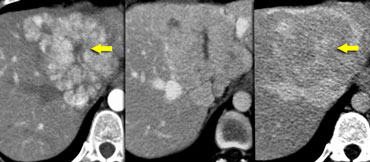

Two FNHs with late enhancing central scar Two FNHs with late enhancing central scar

Focal Nodular Hyperplasia (FNH)

On the left two adjacent hypervascular lesions with homogeneous enhancement in arterial phase and hypodense central scars in arterial and venous phase, which enhance in the equilibrium phase.

This is characteristic of FNH.

Notice that the small FNH, which is anterior and right to the bigger one, has the same enhancement pattern.

At late arterial phase, FNH typically presents with a bright homogeneous enhancement, but less intense than the aorta with a hypodense central scar.

Smaller ( The radiating hypodense fibrous bands or septa, arising from the scar, are not infrequent and quite characteristic.

At portal phase, FNH is often iso-attenuating to the normal liver and may be difficult to deliniate.

Delayed phase often shows hyperattenuation of the central scar and septa due to late opacification of the fibrotic components.

No calcifications, inhomogeneity or capsule should be seen in FNH.